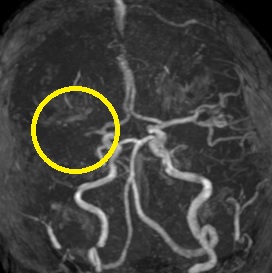

ろれつ困難と左半身重度麻痺のため当院に救急搬送となった患者様に対し、発症2時間30分でt-PAの投与を開始。t-PA開始1時間半後に左麻痺とろれつ困難は回復し始め、翌日には症状は消失。t-PA後のMRA検査で閉塞血管の完全再開通を認め、発症から2週間後に神経症状なく退院。

右大脳動脈閉塞(来院時MRA検査画像)

t-PA静注後